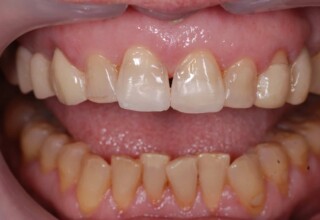

Composite Resin Veneers

Resin veneers are an inexpensive mode of esthetic improvement of anterior teeth, premolars also. Their potential is admirable and their limit is the operator’s clinical dexterity and imagination. In this case there were multiple problems with the upper four incisors: staining, poor inclinations, diastemas, multishading, poor interrelationship and poor tooth-gingiva ratios. They were restored with four direct composite resin veneers (one on a porcelain implant crown!) which were manufactured intraorally!!!